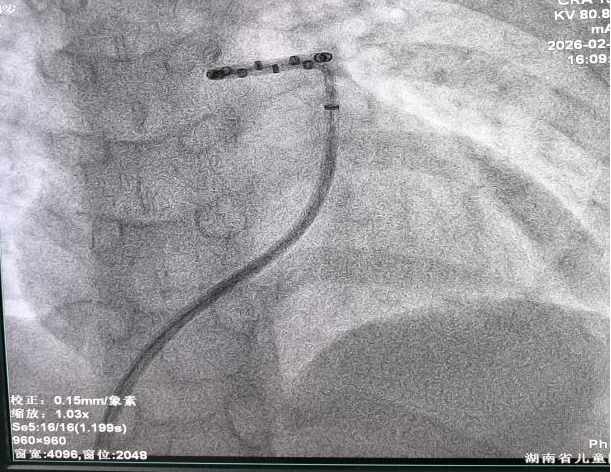

手术由心脏中心二病区肖云彬教授、杨舟教授主刀,在麻醉与监护保障下完成精准消融操作。术后即刻评估显示,小涵平均肺动脉压较术前下降26%,肺血管阻力下降17%。小涵术中及术后生命体征平稳,目前恢复良好,顺利出院。

本次手术体现了儿童PADN手术的显著技术挑战和重要突破。肖云彬表示,儿童肺动脉结构纤细,血管壁薄,且长期高压状态下常伴有血管形态改变,对术中的导管操作和消融定位提出了极高要求。儿童青少年处于生长发育关键期,手术需在追求即时血流动力学改善的同时,充分考虑长期生长发育影响。为此,该院在术前由医务部牵头,组织心脏中心、麻醉科、影像科、伦理委员会等多部门进行了系统严谨的技术论证和伦理审查,并特邀南京市第一医院张航教授参与指导,制定了完善的手术预案。